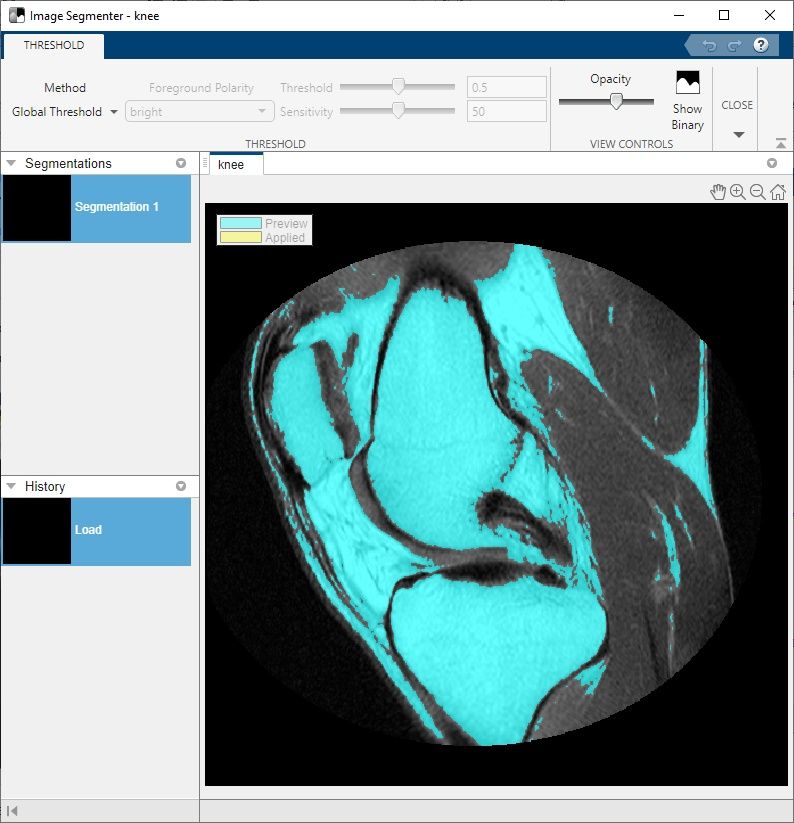

Screenshot of the Image Segmenter app with controls for threshold method and opacity.

Using thresholding in the Image Segmenter app in Image Processing Toolbox to segment the bone from the soft tissue in an MRI image of a knee.